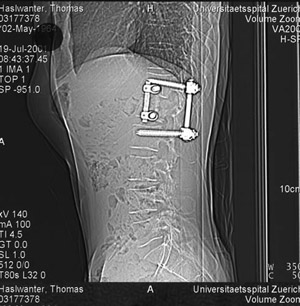

(in German) On April 25 2001, over lunch in a climbing gymn, Sarah

missunderstood me, and - instead of lowering me - she disengaged

the rope. I fell 12 m, backward. The impact shattered my top lumbar

vertrebra, compressing my spinal cord. They got me into hospital

fairly quickly. Jean, my wife, was told I'd be in a wheelchair.

I wasn't - but only by 1 mm of nerve fibers, which survived the

accident ....